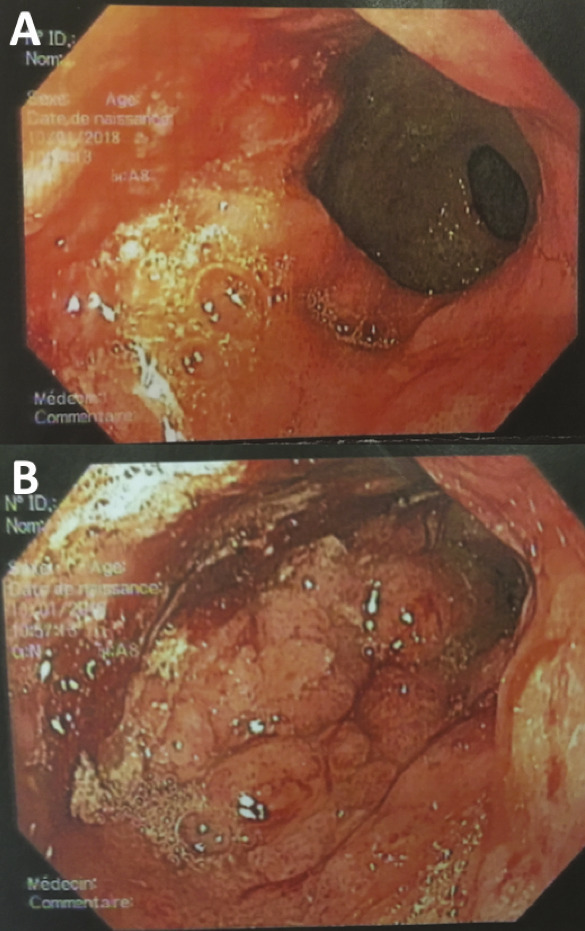

Un mois et demi plus tard, devant la persistance des symptômes et la perte de 6 kg supplémentaires, une tomodensitométrie est réalisée, qui montre un aspect épaissi de la paroi gastrique mesurant 17 mm d’épaisseur, limité à l’antre gastrique. Une nouvelle endoscopie œsogastroduodénale est alors réalisée, qui ne note pas d’anomalie évidente, si ce n’est toujours un aspect rigide à l’insufflation. Une écho-endoscopie haute est réalisée, qui révèle un épaississement localisé de la paroi gastrique et permet des biopsies guidées qui décè- lent la présence d’un adénocarcinome gastrique avec présence de cellules indépendantes.

De même, une confusion fréquente est faite entre le type histologique ADCI et la linite gastrique. Cette dernière est définie macroscopiquement, en anatomopathologie, en endoscopie (fig. 2) ou en imagerie (fig. 3), par un aspect épaissi et rigide de la paroi gastrique. L’aspect de linite est fréquemment associé au type histologique ADCI, comme cela a été noté dans une série de 27 linites gastriques analysées par deux anatomopathologistes différents. P armi ces linites, 21 étaient des adénocarcinomes gastriques à cellules indépendantes et 6 d’autres types histologiques selon la classification de l’OMS. Après une troisième lecture des lames, il apparaissait que 4 tumeurs avaient un contingent minoritaire de cellules isolées (< 50 %) et 2 tumeurs étaient des adénocarcinomes tubulaires.3